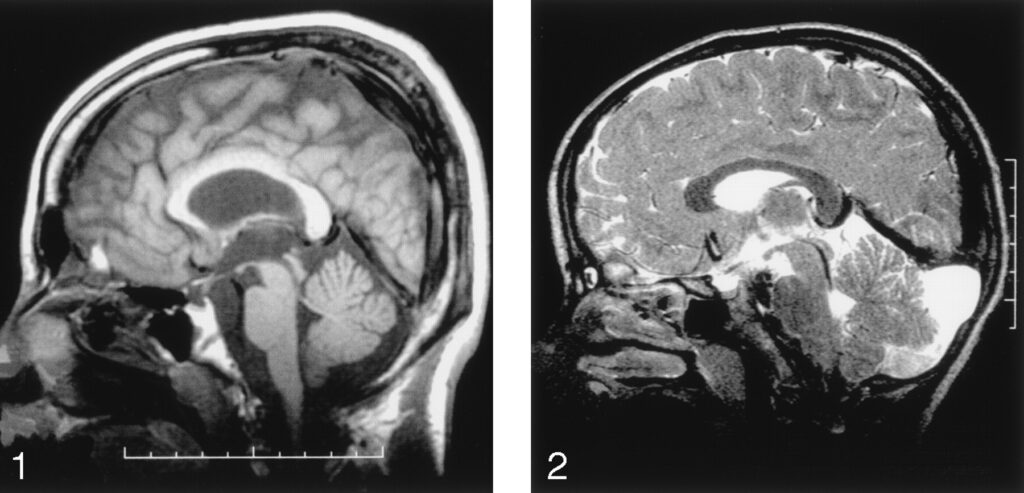

- MRIなどで小脳・特に虫部(vermis)あるいは小脳萎縮の所見を確認することがあります。 AJNR